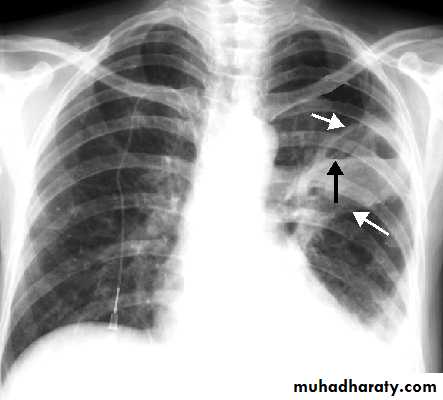

Lung abscess (investigations)

Chest X-ray (and CT scan) shows:homogenous lobar or segmental opacity consistent with consolidation or collapse.

Abscess is characterized by cavitation and fluid level.